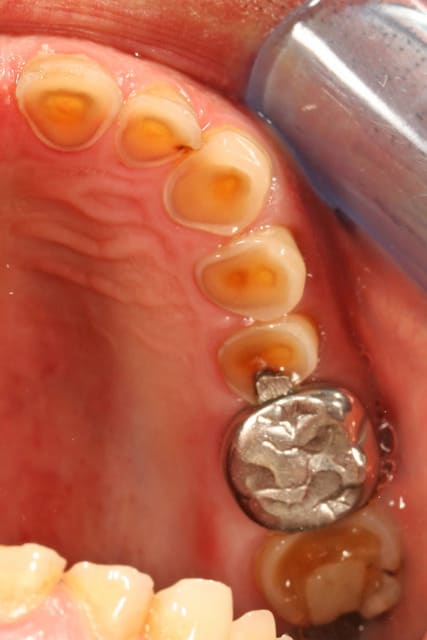

les modèles d'étude

on voit bien l'abrasion liée au bruxisme

l'érosion liée à l'acidité (une bière tous les soirs avant le repas, une pomme tous les soirs en dehors du repas)

l'usure des prémos liée a de mauvaises habitudes dans son métier (tournevis ou stylo au coin de la bouche)